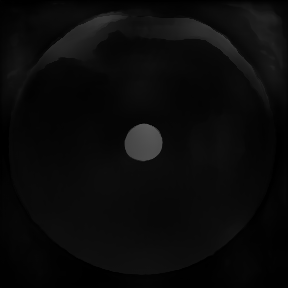

3.6.2 Data

As examples for PA image reconstructions, we show in Figure 12 reconstructed images containing estimated distributions of the optical absorption coefficient from cross-sectional photoacoustic images of piecewise-constant test objects (phantoms), cf. (citep \@BBN(Grohl et al., 2023)). These images were the result of a two-stage process to solve the PA inverse problems. PA data was acquired with a commercial photoacoustic imaging system (MSOT InVision 256-TF, iThera Medical GmbH, Munich, Germany) and processed with three different algorithms (referred to as Alg1, Alg2, Alg3). For the visualization and assessment the outputs of the algorithms where clipped with the reference image’s maximum.

Alg1 corrects a reconstructed PA image by using the light fluence obtained from simulations based on the reference measurements. Alg2 and Alg3 are deep-learning algorithms that are trained to directly estimate the absorption coefficient from the reconstructed image. Alg2 was trained with simulated data and Alg3 was trained with experimental data. The reference absorption coefficients are obtained by using a double-integrating sphere (citep \@BBN(Pickering et al., 1993)) setup as a complementary measurement system, which only yields point estimates for homogeneous material samples. Because of the piecewise-constant nature of the used phantoms, one can fabricate an additional batch of the material used for the test object, measure it, and relate the calculated properties to the test object. For any complicated objects or in vivo images, this process would be unfeasible.

Refer to caption

(a) Reference 1

(b) (25.1, 0.49, 0.18)

(c) (21.3, 0.81, 0.27)

(d) (22.5, 0.97, 0.07)

(e) Reference 2

(f) (13.1, 0.40, 0.49)

(g) (12.5, 0.67, 0.47)

(h) (12.5, 0.82, 0.23)

Figure 12: Two examples of photoacoustic images, ground truth images (a)(e) and comparisons of the reconstructions with Alg1 (b)(f), Alg2 (c)(g) and Alg3 (d)(h). None of the measures was able to assess the relevant quality for both examples correctly.

FR-IQA mismatches

Photoacoustic images are typically sparse, as few endogenous contrast agents exist, which complicates the application of image-based quality measures. In the original paper (citep \@BBN(Grohl et al., 2023)) the qualitative assessment was conducted manually. In their assessment, Alg3 should perform best, Alg1 second best, and Alg2 worst across the test images. As this kind of manual assessment is not feasible for larger data sets, and may naturally also introduce inconsistencies as well as biases, automated FR-IQA is needed. However, when PSNR and SSIM are applied to the images these intended results cannot be reproduced. SSIM wrongly assesses that Alg1 performs worst throughout all both images (Figure 12), LPIPS for the second example. PSNR wrongly judges Alg1 as the best rather than Alg3 and does not give much lower results for Alg2 than Alg3, despite the introduction of artefacts that lead to a significant degradation of image quality.

Depending on the goal of the data analysis, the meaning of image quality changes here. On the one hand, artefacts might introduce structures into the image that could be mistaken for regions of interest. On the other hand, an inaccurate estimation of the absolute absorption coefficient might lead to errors in the estimation of functional tissue parameters. Functional tissue parameters, such as blood oxygenation, are important to assess the health status of a patient. Suitable IQA measures would be very helpful here, to avoid medical decision-making or treatment planning based on inaccurate reconstruction results.

Therefore, targeted IQA measures that are indicative of success given a desired use case are required for the objective assessment of algorithms for quantitative PAI. In particular, meaningful objective comparison of reconstruction algorithms would be highly valuable to allow fast advances in the still challenging field of PAI. In addition to the FR measures in the development stage, it would be beneficial to agree on a set of suitable NR measures usable on patient data without ground truth data.